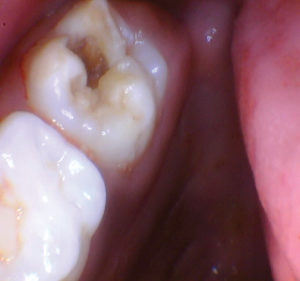

Caso 1

Un paciente de 8 años presentó descomposición de OD en un primer molar primario con síntomas de pulpitis reversible. El diente fue el tratamiento planificado para una restauración de OD con Activa Bioactive Restorative (Pulpdent). Tras la excavación por descomposición, se produjo una exposición pulpar que requirió una pulpotomía terapéutica. Debido a la edad del paciente, me sentí cómodo con una pulpotomía terapéutica con Biodentine (Septodont) seguida de una restauración estética. Si el paciente hubiera tenido entre cuatro y cinco años, me habría restaurado con una corona de acero inoxidable debido a su historial comprobado de longevidad.

Figura 1 Vista preoperatoria del primer molar primario superior. |